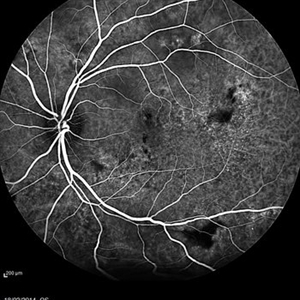

Multifocal Exudative Detachments Due to VKH

May 14 2014 by Avris Romario Diparaja Siahaan

Blue auto fluorescence fundus photograph a 38-year-old man with multifocal CSR and inferior exudative retinal detachment on both eyes (Harada Syndrome). This patient has underwent a photocoagulation laser on both eyes.

Photographer: Avris Romario Diparaja Siahaan, Klinik Mata Nusantara

Imaging device: Heidelberg HRA + OCT Spectralis

Condition/keywords: autofluorescence imaging, multifocal central serous chorioretinopathy (CSCR)